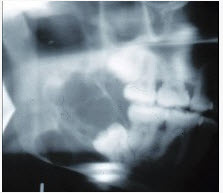

女,32岁,右下后牙龈向外膨隆,后牙渐松动3个月。X线片(如图)示右下颌磨牙区颌骨呈蜂房样改变,病变区牙根呈锯齿状吸收。该病人最可能的诊断是()

A、右下颌骨角化囊肿

B、右下颌骨骨巨细胞瘤

C、右下颌骨骨肉瘤

D、右下颌骨成釉细胞瘤

E、右下颌骨中央性颌骨癌

D